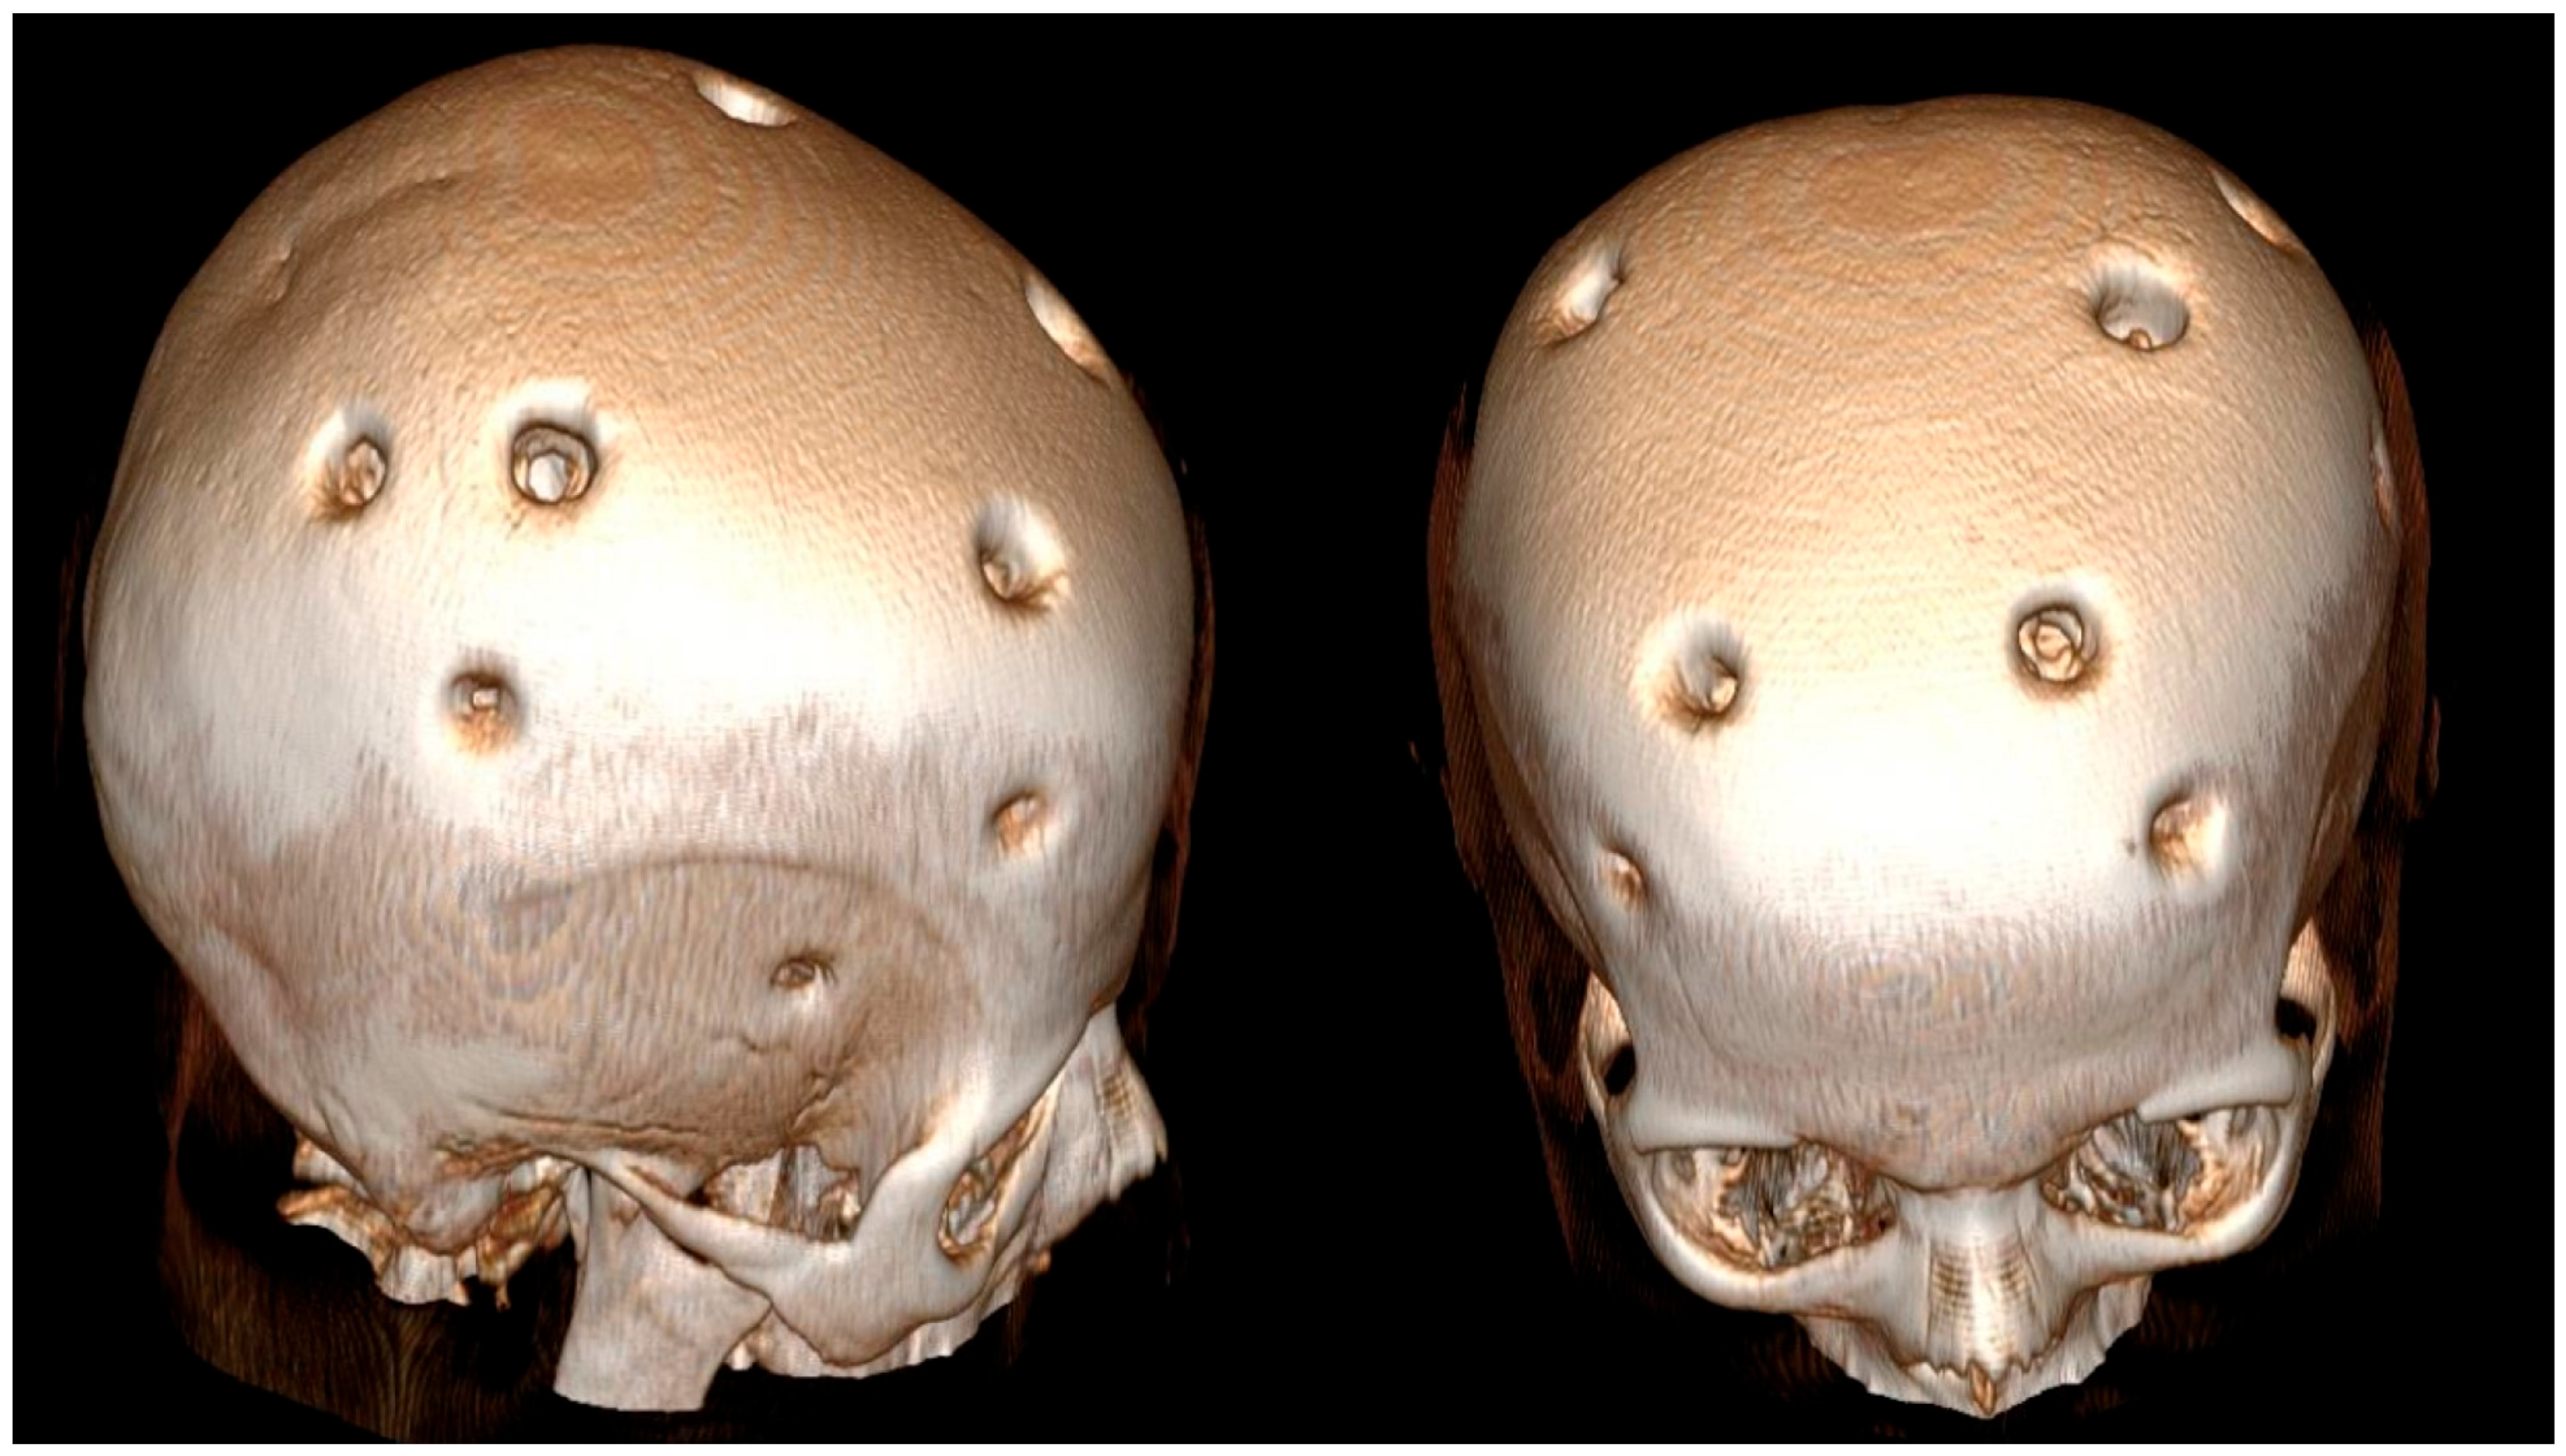

According to the history obtained from her husband, the patient had experienced a hemorrhagic stroke 15 years earlier, at which time MR angiography had confirmed the diagnosis of MMD, and she underwent multiple burr hole surgery (Figure 3 and Figure 4).

Figure 4. Three-dimensional brain CT reconstruction obtained 15 years after indirect revascularization, demonstrating the patient’s appearance following the multiple burr hole (MBH) procedure.